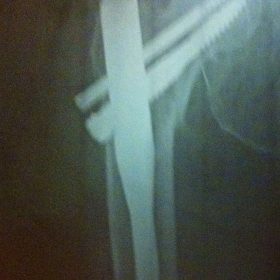

Διατροχαντήριο : Εξωαρθρικό κάταγμα, στην περιοχή ανάμεσα στο ελάσσονα και το μείζονα τροχαντήρα. Αντιμετωπίζεται χειρουργικά με ενδομυελική ήλωση τύπου γ-Nail. Δύο τομές 3 εκατοστών και 1 εκατοστού αντιστοίχως για την εισαγωγή και το κλείδωμα του ήλου μέσα στο οστό. Η μέθοδος είναι κλειστή,σχεδόν αναίμακτη,διάρκειας 30 λεπτών,με τη βοήθεια C-ARM (τηλεόρασης). Στον ασθενή παρέχεται οπτικό υλικό (όλα τα χειρουργικά στάδια) σε CD ή Στικάκι,λόγω της δυνατότητας καταγραφής του χειρουργείου από το C-ARM Ο ασθενής περπατάει άμεσα μετεγχειρητικά στις 5 ώρες μετά την επέμβαση και εξέρχεται από το νοσοκομείο σε 1 -2 ημέρες.

Υποτροχαντήριο :Εξωαρθρικό κάταγμα κάτω από τον ελάσσονα τροχαντήρα του μηριαίου οστού. Αντιμετωπίζεται χειρουργικά με ενδομυελική ήλωση τύπου Long γ-Nail. Δύο τομές 3 εκατοστών και 1 εκατοστού αντιστοίχως για την εισαγωγή και το κλείδωμα του ήλου μέσα στο οστό. Η μέθοδος είναι κλειστή,σχεδόν αναίμακτη,διάρκειας 60 λεπτών,με τη βοήθεια C-ARM (τηλεόρασης). Στον ασθενή παρέχεται οπτικό υλικό (όλα τα χειρουργικά στάδια) σε CD ή Στικάκι,λόγω της δυνατότητας καταγραφής του χειρουργείου από το C-ARM Ο ασθενής περπατάει άμεσα μετεγχειρητικά στις 5 ώρες μετά την επέμβαση και εξέρχεται από το νοσοκομείο σε 1 -2 ημέρες.